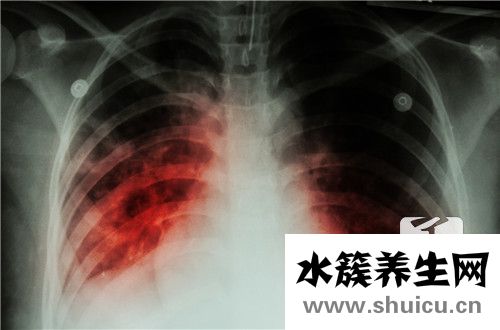

大家都知道人體內有很多炎癥性疾病,但大多數人并不清楚炎癥臨床表現的全過程。比較常見的炎癥是由感染因素引起的,比如肺炎、腎炎、肝臟炎癥,大家都比較熟悉。當這種人體器官發炎時,身體會開始自己的防御過程,然后出現一系列的臨床表現,整個過程會有詳細的改變。

發炎的基本臨床表現一般 歸納為部分組織的霉變、外滲和增生。

一般說來,炎癥反應或發炎的初期,通常滲出性和霉變占位性病變較明顯,而炎癥或發炎的中后期,則增生占位性病變較突顯。

發炎的基本臨床表現是霉變、外滲和增生。組織和體細胞的轉性、壞死統稱霉變,僅是基本臨床表現的一部分內容;而紅、腫、熱、痛和功能問題則意味著著發炎的外界主要表現;發炎組織的炎癥性血腫和水腫只包括了發炎的一部分血管轉變和液體外滲,不可以包含發炎的基本臨床表現;而周邊血白細胞多和發炎地區白細胞計數侵潤則意味著了一部分發炎的全身反映和部分炎體細胞侵潤,都不全方位。